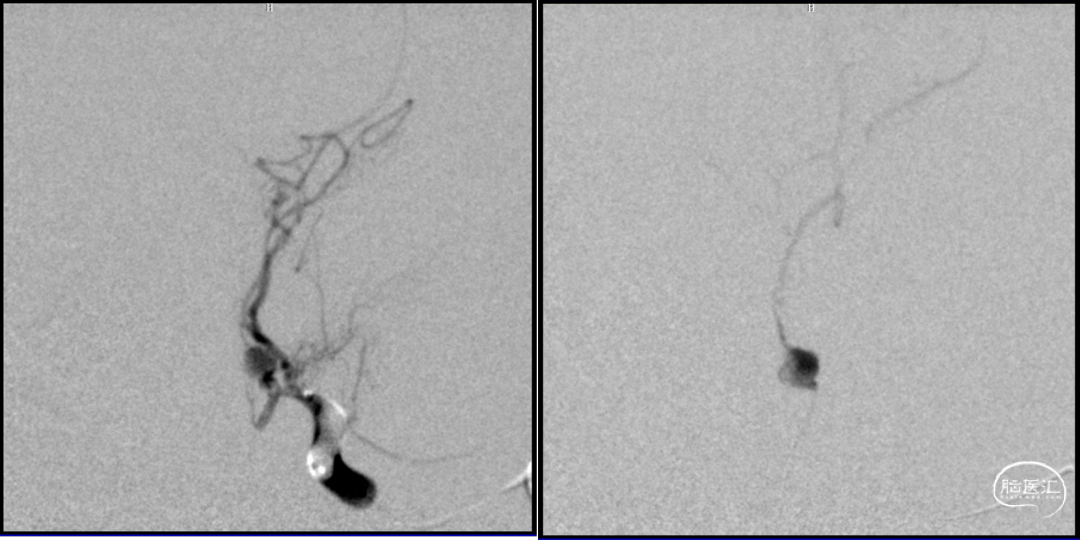

2023-08-30

术后造影:假性动脉瘤消失

2023-08-31

术后CT

术后MR未见该中央新发支梗塞

后交通动脉在向后稍内行走的过程中发出两组约2 -8条(以4条为多见)细小的中央支(图1)。前组供应丘脑下部、丘脑腹侧部;视束前部和内囊后肢。后组主要供应丘脑底核。这些中央支之间虽然存在吻合,但其中一支阻塞后,因有效的侧支循环难以建立,故多产生相应供应区的梗死。该病例栓塞假性动脉瘤所在中央支没有症状,考虑为假性动脉瘤导致该中央支缺血耐受和血管代偿。